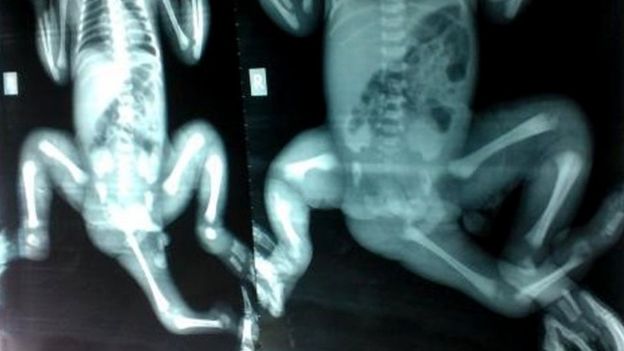

Un equipo de cirujanos pasó meses reconstruyendo la anatomía de la niña. “Una gemela había crecido fuera de su pelvis, pero sólo era una parte de gemela. El problema era que no había ninguna regla para esto, en la medida en que era un caso totalmente único”, explicó a la AFP Chris Kimber, jefe de cirugía pediátrica en el hospital para niños Monash.

Tras consultar a expertos de Europa y Estados Unidos, los cirujanos idearon una operación para retirar los restos de la tercera pierna, de la que una parte había sido cortada en Bangladés, y quitar y reubicar otros órganos.

Varias partes del cuerpo de una gemela se habían desarrollado en el suelo pélvico de la niña.

Los cirujanos pasaron muchas horas examinando a la niña y descubrieron que tenía distintos órganos duplicados: el recto, el ano, la vagina y el útero. Además Choity era incontinente.